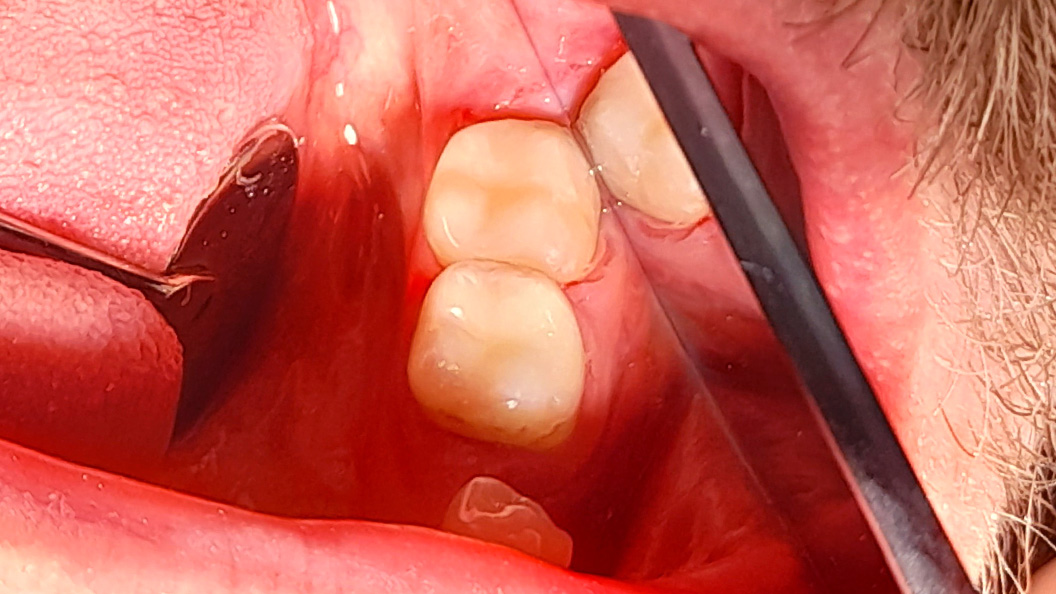

До и после лечения

В «Стоматологию Комфорта» обратился пациент с жалобами на наличие кариозных полостей и кратковременную боль от холодного в области 37 и 38 зубов. Терапевт Похилько Надежда Геннадьевна в ходе осмотра выявила кариозные поражения на окклюзионной и вестибулярной поверхностях 37 зуба, а также на окклюзионной и мезиальной поверхностях 38 зуба. Зондирование было болезненным. После препарирования полостей под контролем кариес-маркера, врачом был поставлен диагноз: глубокий кариес 37 и 38 зуба. Было принято решение о лечении с дальнейшей постановкой пломб из композита светового отверждения Estelite.

- постановка пломб из композита Estelite.